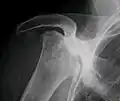

X-ray images of avascular necrosis in the early stages usually appear normal. In later stages it appears relatively more radio-opaque due to the nearby living bone becoming resorbed secondary to reactive hyperemia.[2] The necrotic bone itself does not show increased radiographic opacity, as dead bone cannot undergo bone resorption which is carried out by living osteoclasts.[2] Late radiographic signs also include a radiolucency area following the collapse of subchondral bone (crescent sign) and ringed regions of radiodensity resulting from saponification and calcification of marrow fat following medullary infarcts.

-

Radiography of total avascular necrosis of right humeral head. Woman of 81 years with diabetes of long evolution. -